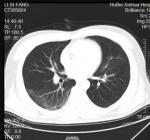

复查胸部CT示病灶较前明显吸收(图2-3-4)。连续2次新型冠状病毒核酸检测均阴性,于此日出院。

图2-3-4 2020年2月11日胸部CT